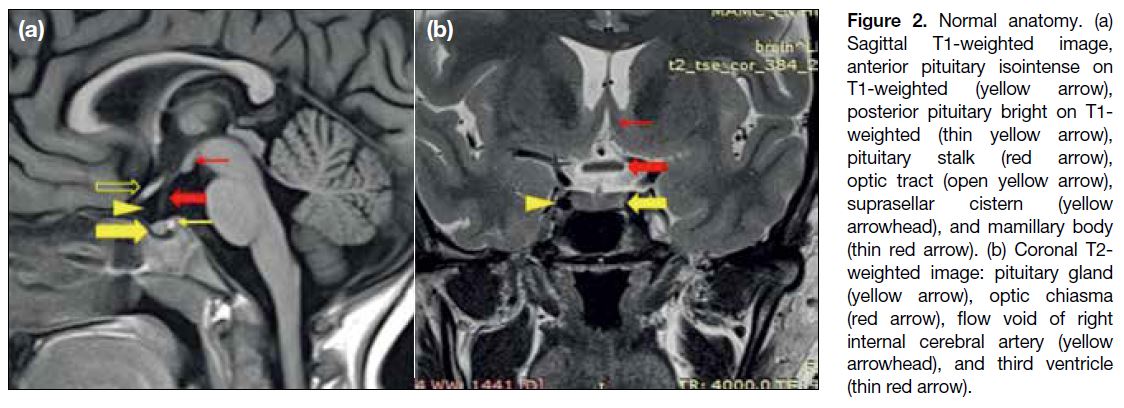

The sellar, suprasellar, and parasellar regions are an

anatomically complex area (Figure 2). The pituitary fossa is a spherical depression in the sphenoid bone,

bounded by the sphenoid sinus antero-inferiorly, the

cavernous sinuses laterally, diaphragm sellae and the

hypothalamus superiorly, and dorsum sellae and the

brainstem posteriorly. The suprasellar cistern is an

expansion of the subarachnoid space and contains

the optic nerves, chiasma, tracts, Circle of Willis, and

pituitary stalk / infundibulum. The hypothalamus forms

the floor and lateral walls of the third ventricle. The tuber

cinereum is a ridge of tissue between the infundibulum

and mammillary bodies. The pituitary gland is composed

of two parts: the adenophysis, isointense to brain on both

T1-weighted (T1W) and T2-weighted (T2W) images

and the neurohypophysis, seen as a bright spot on T1W

images. The anterior lobe appears hyperintense like the

posterior lobe in newborns and becomes T1 isointense

by 6 to 8 weeks of life.[3]

Figure 2. Normal anatomy. (a)

Sagittal T1-weighted image, anterior pituitary isointense on T1-weighted (yellow arrow), posterior pituitary bright on T1-weighted (thin yellow arrow), pituitary stalk (red arrow), optic tract (open yellow arrow), suprasellar cistern (yellow arrowhead), and mamillary body (thin red arrow). (b) Coronal T2-weighted image: pituitary gland (yellow arrow), optic chiasma (red arrow), flow void of right internal cerebral artery (yellow arrowhead), and third ventricle (thin red arrow).